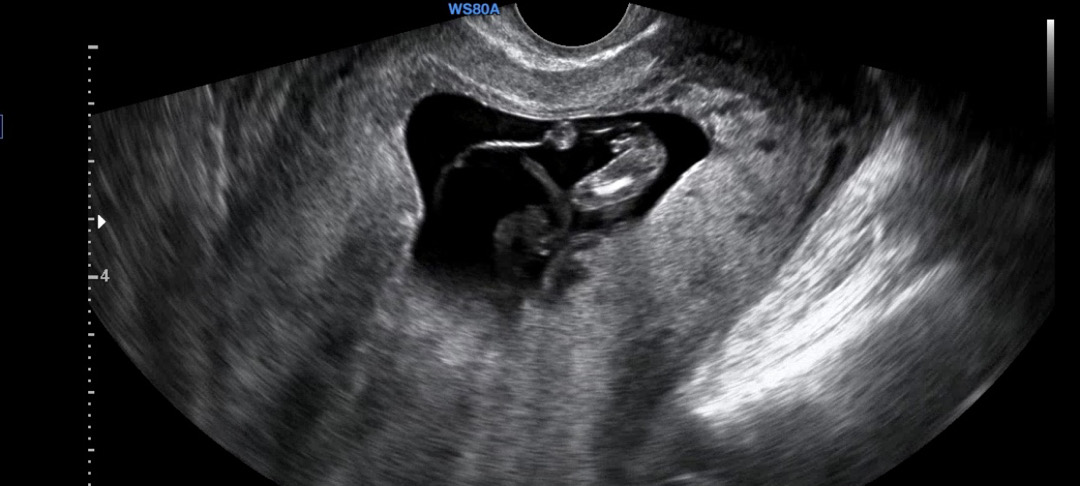

몇주예요 ? 근데 끝에가 갈라졌네용 ?

다리사이에 아무리 봐도 아들같은데 어떻게 보이시나요?

12주에요 ㅎㅎ

맞아요 ㅎㅎ 그래서 고츄인지.... 뭔지..ㅠ

툭 튀어나온건 아들같은데 끝에가 다른애들보다 쫙 벌어져서 딸같기두하네욤 ㅎㅎ 저희 첫째가 옆모습로 봣을때 쫙 갈라졌어서요 !